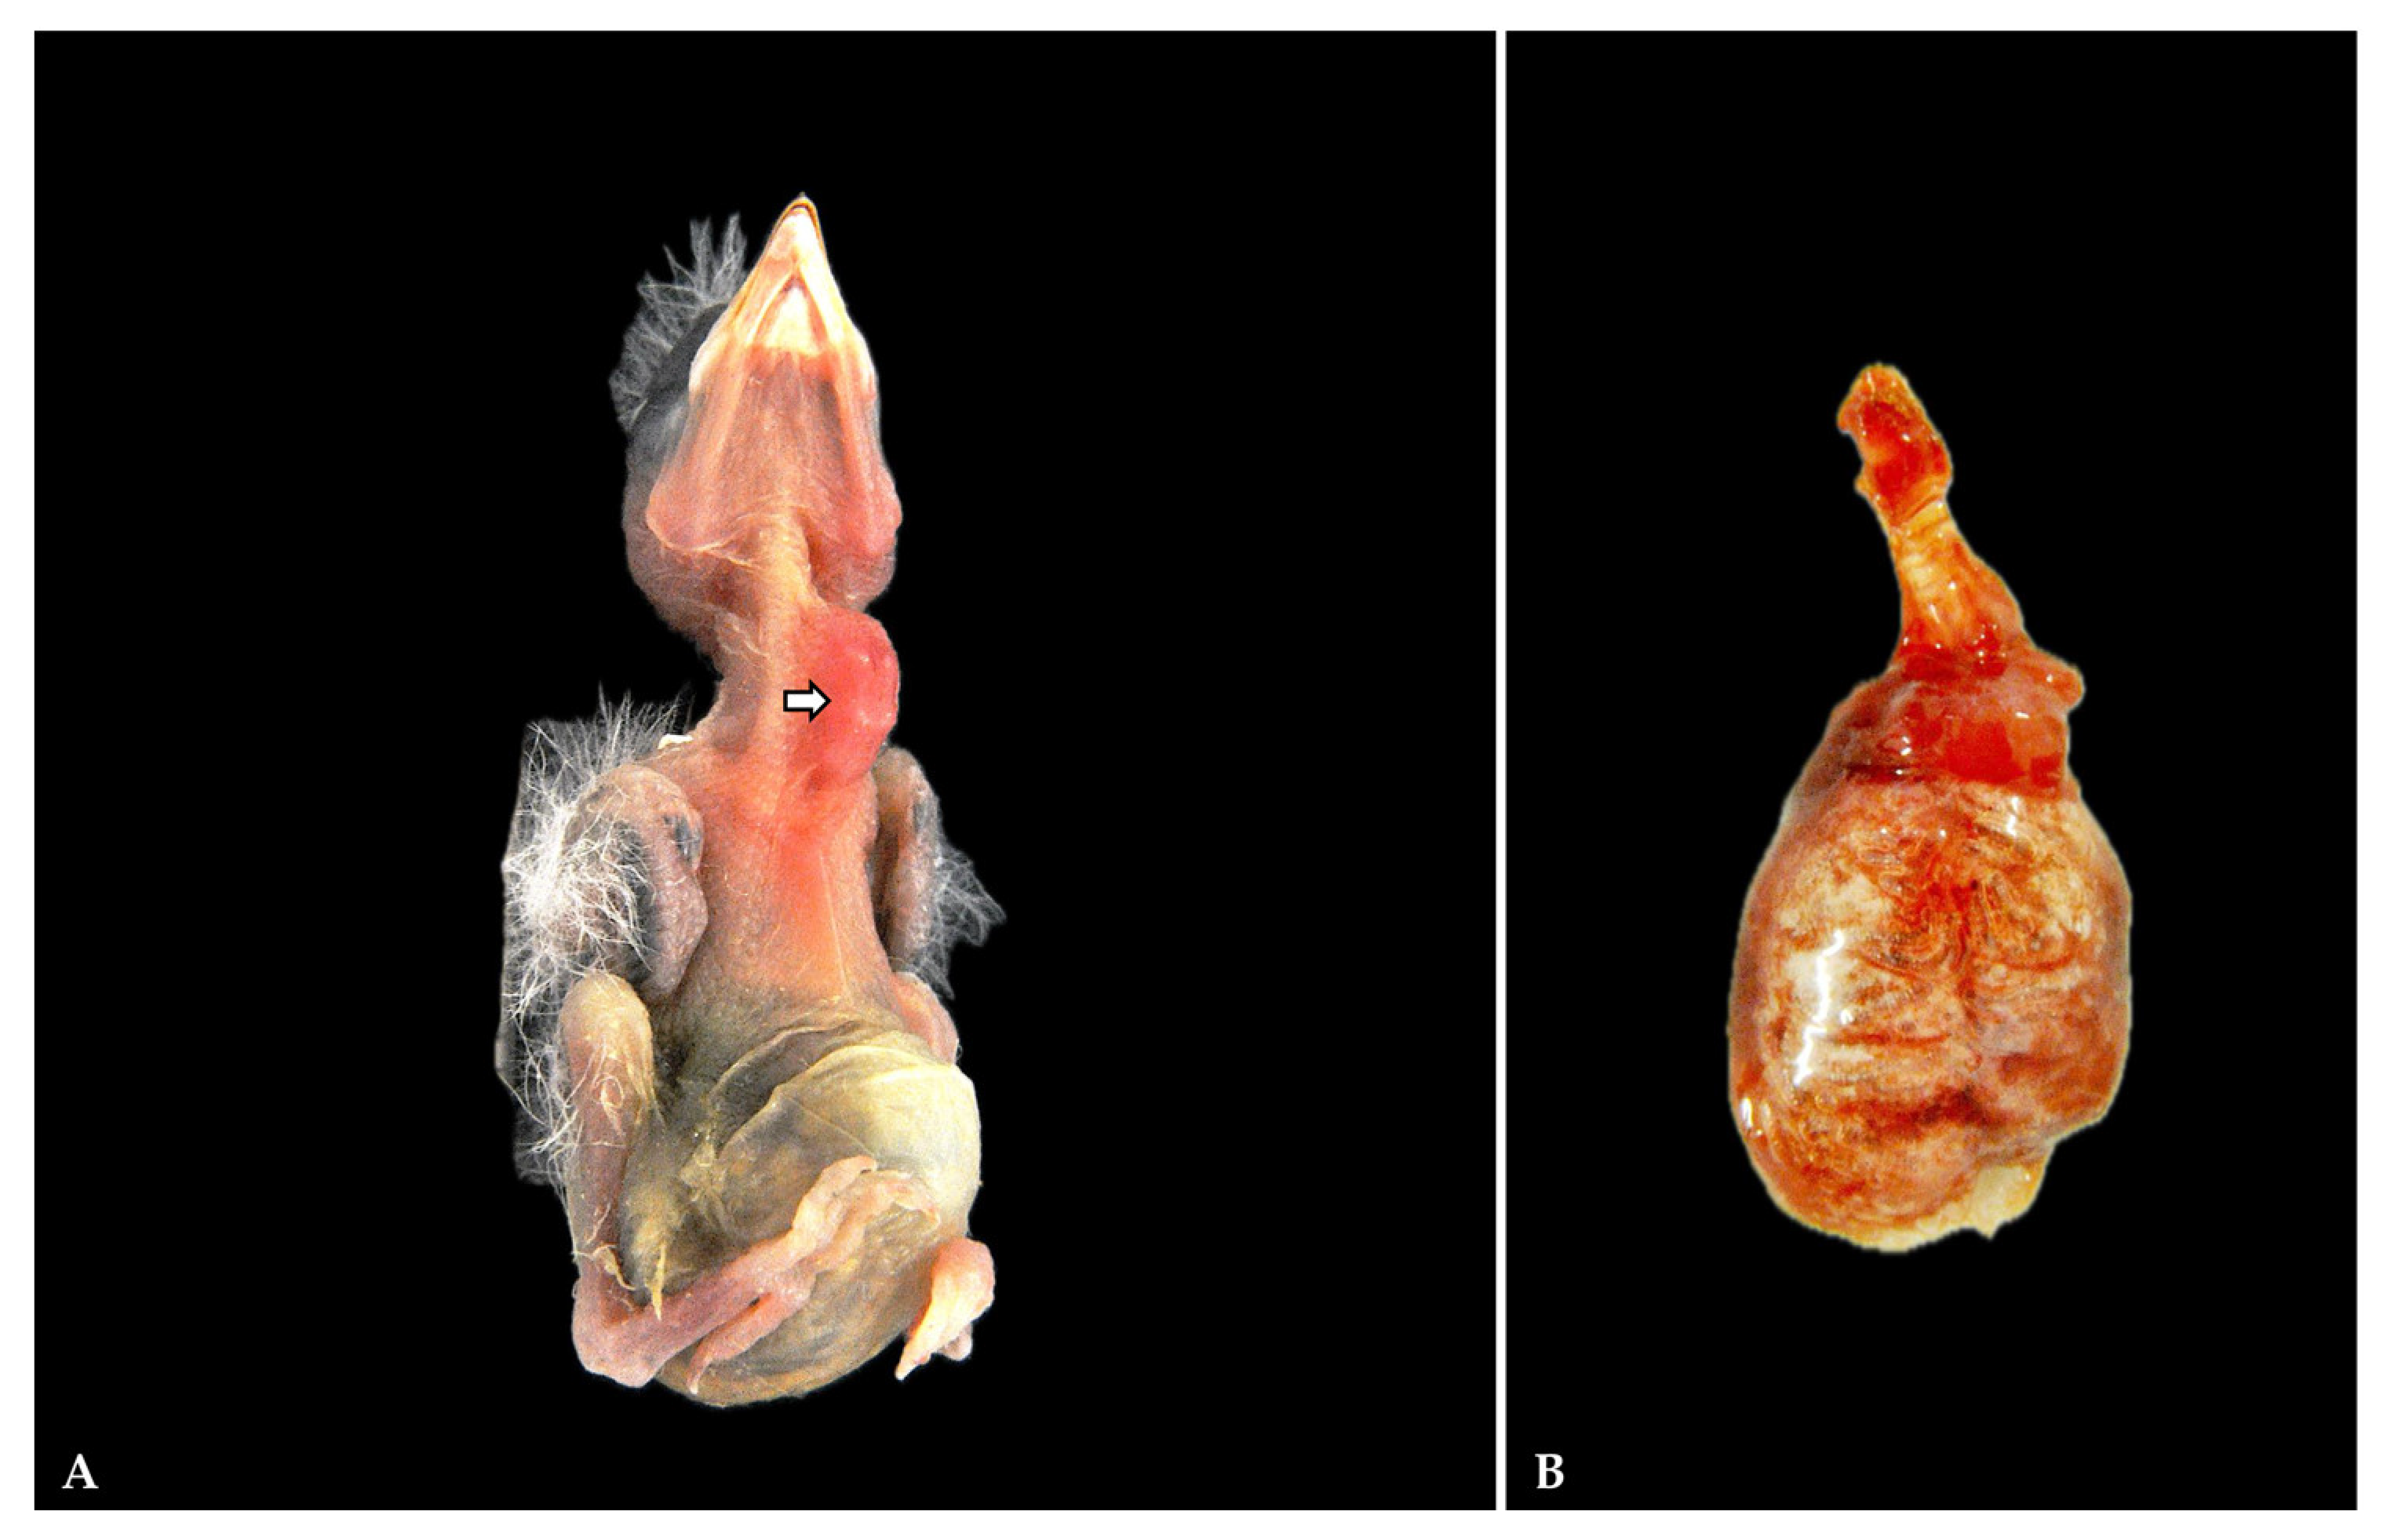

3.1. Gross Pathology